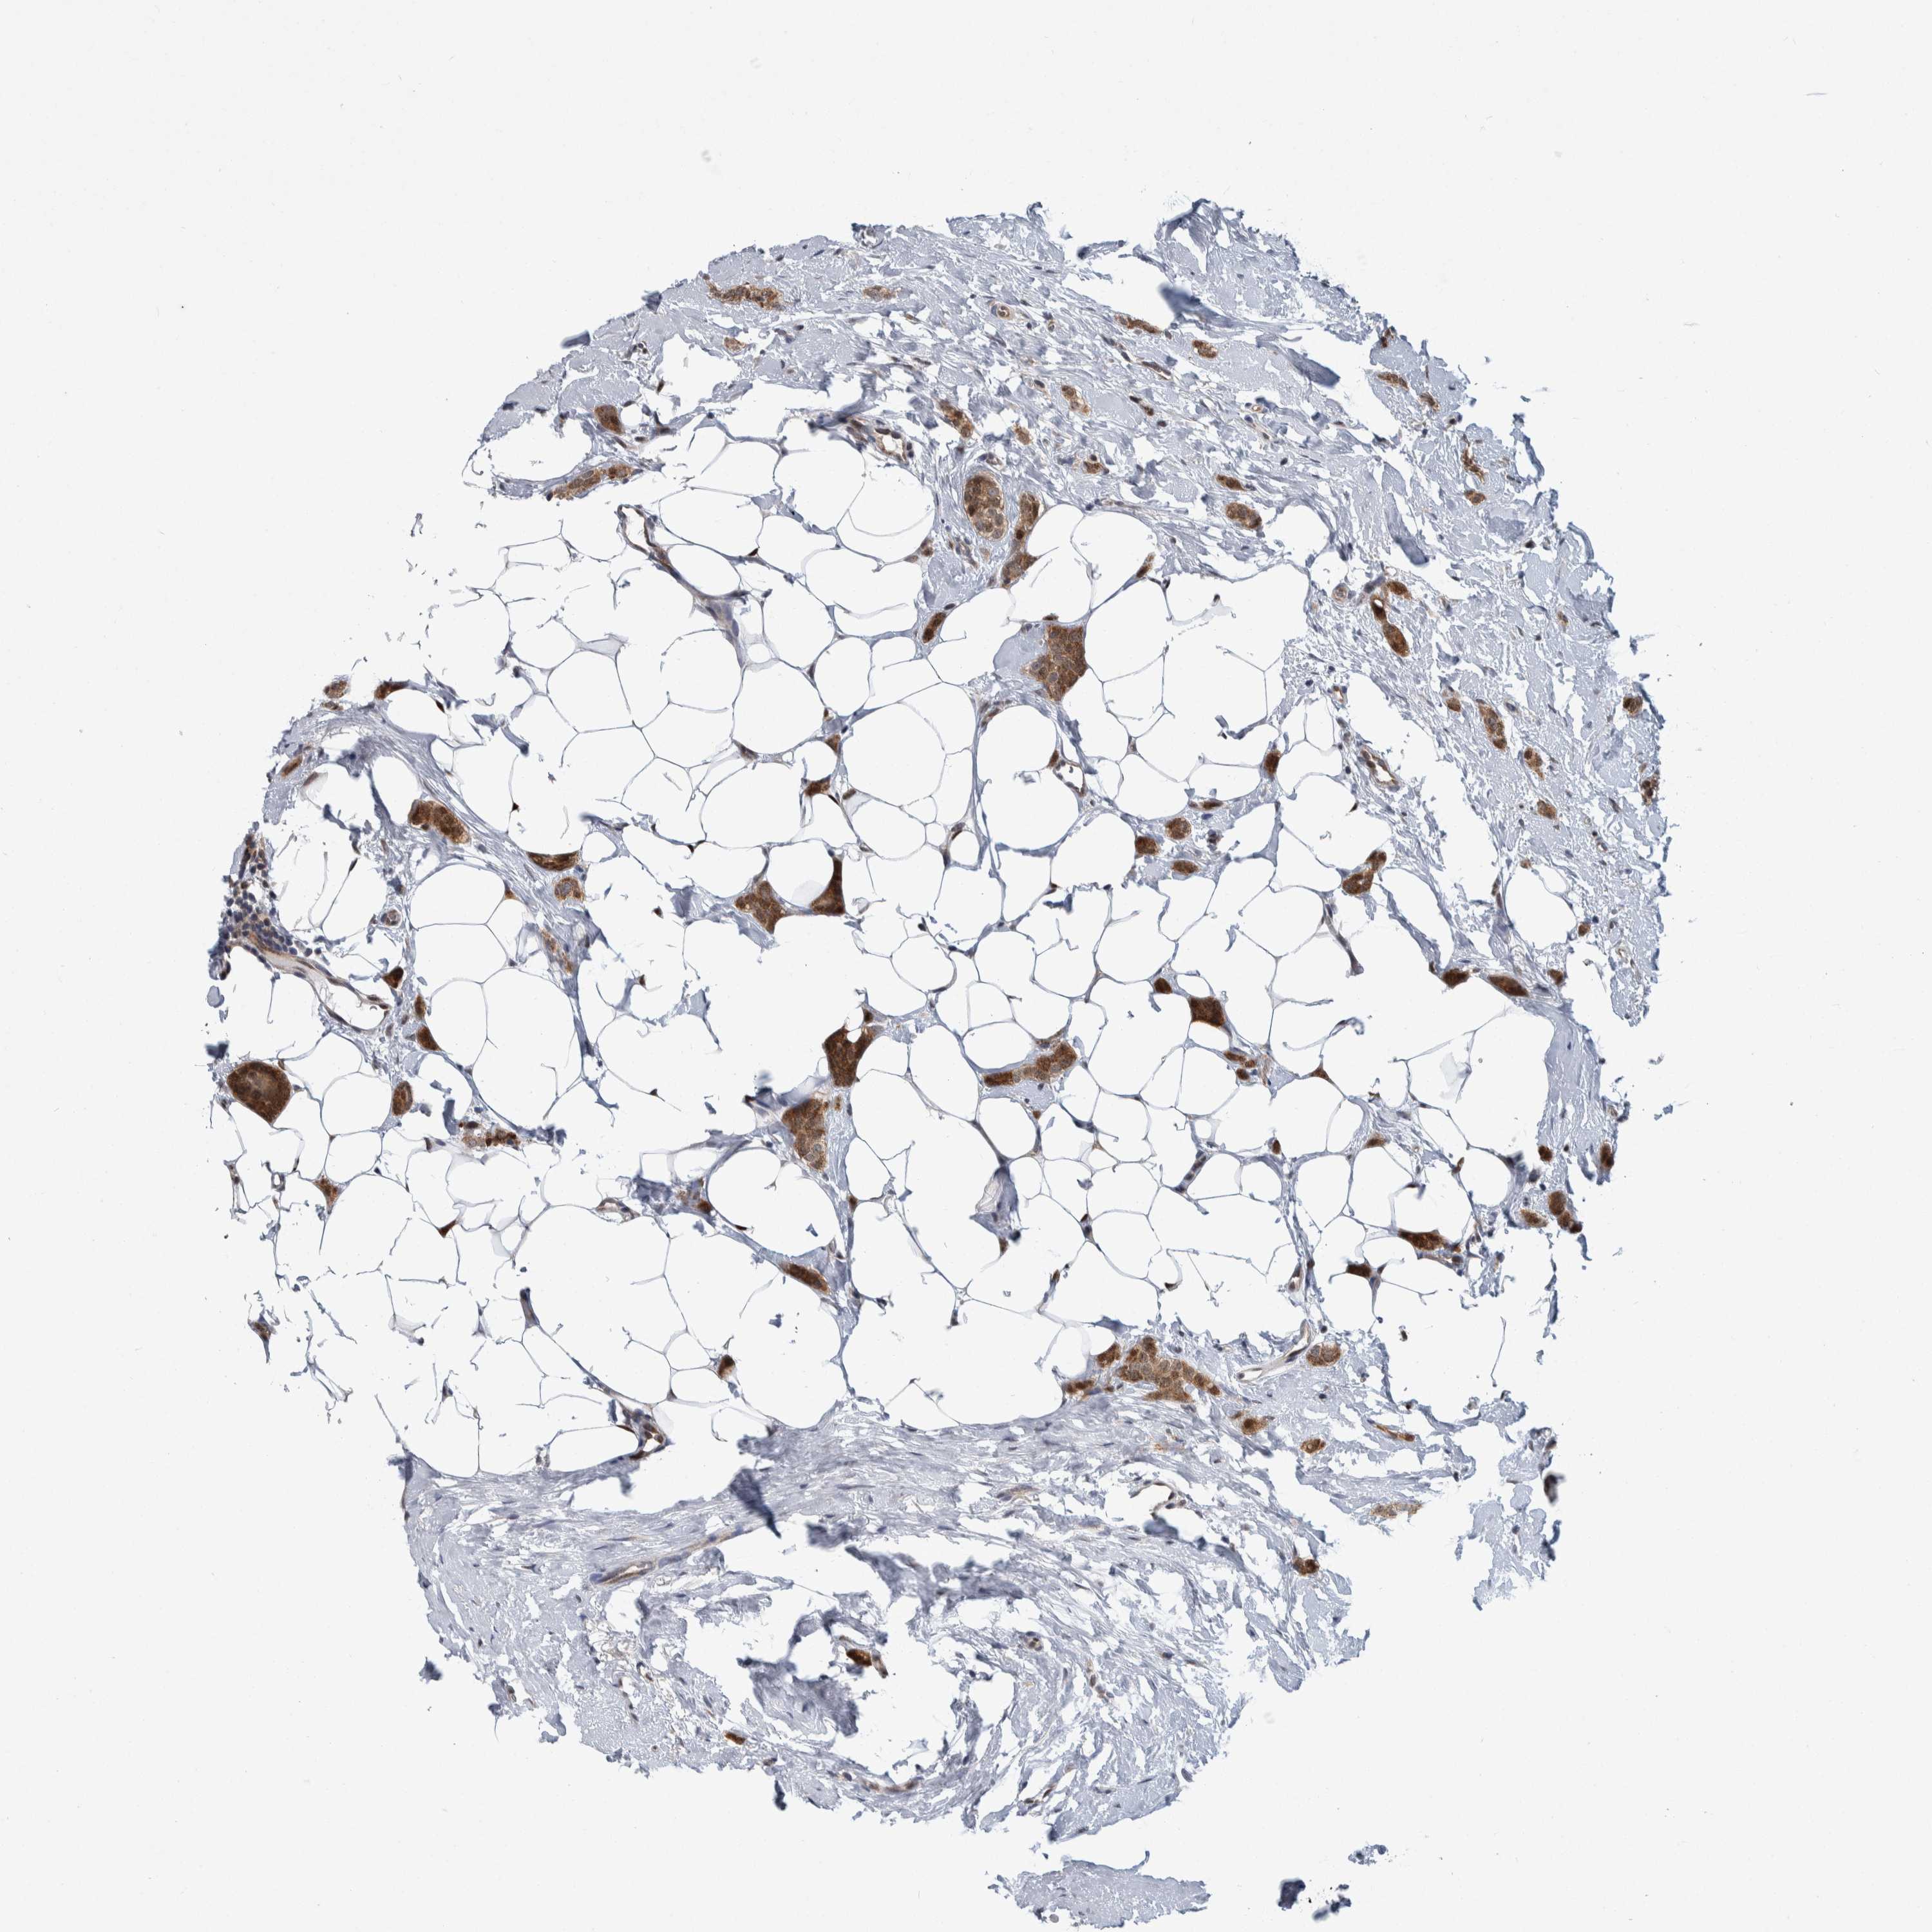

CANCER BREAST CANCER Show tissue menu

BRCA TCGA BRCA VALIDATION PROTEIN EXPRESSION

ANTIBODIES

AND

VALIDATION